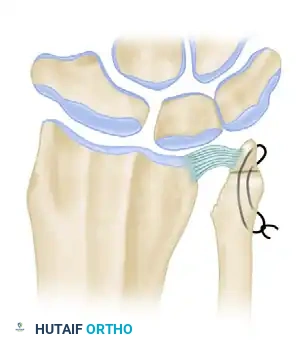

Figure 2: The ulnar head is resected to resemble a tapering dowel, meticulously preserving the ulnar styloid and the critical attachments of the TFCC.

Figure 3 (Bowers A): Demonstration of impingement. Because the ulna is too long relative to the resection, the remaining ulnar shaft impinges on the stylocarpal ligament and the radius during rotation and ulnar deviation.